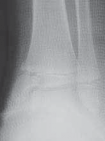

2. For a medially gapped Salter Harris type II abduction injury, a medial approach is used (

TECH FIG 1

).

A B CTECH FIG 1•

Surgical approach to a medially gapped fracture.

A.

This AP radiograph demonstrates a medially gapped Salter-Harris type II abduction-type fracture.

B.

A medial approach is used to obtain open reduction of this fracture.

C.

This operative photograph highlights the periosteum interposed in the physeal fracture, which was extracted to obtain anatomic reduction and prevent medial gapping.